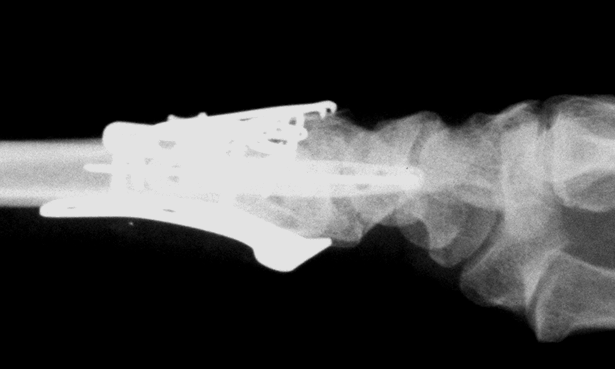

Case 1 Postop